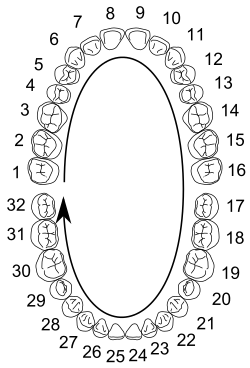

Dental midline

The dental midline is the midsagittal line of maxillary and mandibular dental arches possessing teeth of ideal size, shape, and position, when situated in maximum intercuspation. Each arch also possesses its own midline, which can be used to refer to the location of contact between the mesial surfaces of the central incisors. Thus, if an individual's mandibular teeth are shifted over to the left in a mesial-distal dimension, by 2 mm, for example, that individual's midline would be said to be deviated 2 mm to the left.